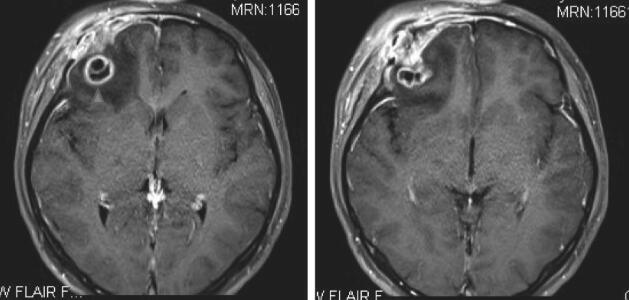

患者,女性,20岁,因“右眼肿痛,伴视物重影1个月,头痛1周”于2018年2月7日入院。2018年1月8日起无明显诱因出现右侧眼睑红肿、胀痛,伴右眼视物重影,无畏光、流泪、流脓,无视野缺损,后红肿逐渐加重,无法睁眼。2018年1月24日至当地医院,考虑“右眼上睑麦粒肿”,给予罗红霉素150mg每天2次,左氧氟沙星液滴眼,妥布霉素/地塞米松眼膏涂右眼,右眼红肿痛继续加重。2018年1月31日开始感右侧额顶部持续性胀痛,无头晕、耳鸣,无恶心、呕吐,无畏寒、发热,至当地医院复诊。行眼眶CT(图1)提示:额骨、眉弓范围软组织肿块伴骨质破坏吸收,并提示右大脑额叶脑水肿、出血可能,拟感染性病变首先考虑;头颅MRI(图2)提示:右侧额骨眼眶外上缘骨质破坏伴右侧额部、颞部、眼睑软组织及右眼上直肌肿胀,右侧额叶环形强化灶伴周围水肿,考虑感染性病变,其他病变待排。

图2 术前头颅MRI

右侧眶上外侧壁及周围软组织内团状混杂信号,内部见囊变坏死区,增强后肿块明显不均匀强化,周围软组织间隙内水肿。右侧额叶内囊实性病灶,增强后实性成分及分隔明显强化,周围可见大片状水肿区